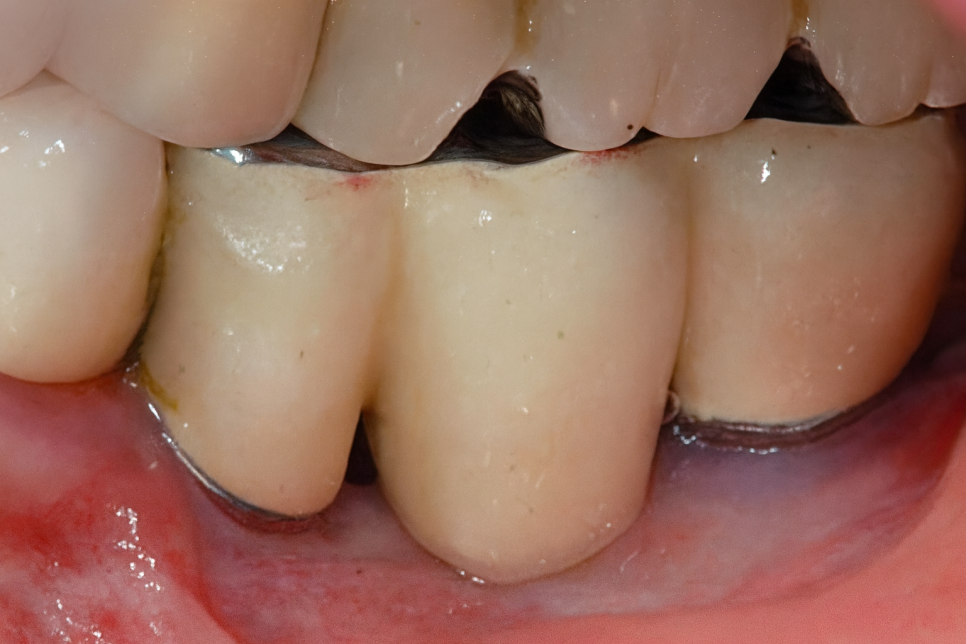

부착치은이란?

다 똑같은 거 아닌가? 생각하실 수 있으나,

다릅니다!

치아와 제일 가까운 곳을 한번 손으로 만져보시면

어느 정도 움직임이 있을 겁니다.

유동성이 있기 때문에 치주낭이라는 주머니가 있죠.

조금 더 윗쪽을 만져보면 아래쪽과 달리

움직임이 없을 겁니다.

이 부분을 [부착치은]이라 부릅니다.

그리고 여길 넘어 더 윗쪽으로 올라가면

다시 말랑한 부분이 있는데

점막이라 부르고 있습니다.

유동성이 있는 곳과 점막 사이,

이 부분이 부착치은인데

충분한 양이 없으면 수명에 영향을 줍니다.

Q. 어떤 역할을 하나요?

앞서 설명드린 부착치은은

"방패"와 같은 역할을 합니다.

뼈와 치아에 단단하게 붙어

안정성과 보호를 제공하는 조직이라,

세균이나 박테리아 등이 침투되지 않도록

1차 방어를 도맡고 있습니다.

첫째, 단단하게 부착되어 임플란트나 치아 주변

구조물을 지지하여 움직임을 최소화하여

'안정성'을 제공합니다.

둘째, 외부 자극이나 세균으로부터

'보호'해줍니다.

셋째, 단단한 잇몸이기 때문에

음식이나 칫솔질 같은 기계적인 자극으로부터

'보호'합니다.

넷째, 잇몸이 내려앉는 퇴축을 예방하며

심미를 증진시켜줍니다.

그래서 오랫동안 건강하기 위해서는

충분한 양이 확보되어야 됩니다.

그런데 발치 후 치조골이 흡수되거나,

염증이 오래 자리를 잡고 있어 골조직이 내려앉는 등

여러 이유로 인하여 잇몸이 소실되면,

보호막 역할을 할 조직이 부족해져

쉽게 세균이 침입하여

염증에 취약한 상태가 될 수밖에 없습니다.

앞서 선유도역 치과 에서 말씀드린 상황에 이르면,

칫솔질이나 음식을 먹는 과정에서 생겨난

작은 충격에도 쉽게 상처가 생겨나고

이 시림이나 통증 같은 증상이 나타나겠죠.

그래서 자연치나 임플란트로

오래 건강하게 유지하려면,

충분한 양을 확보해야 됩니다.